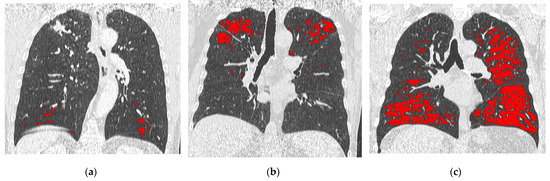

2.2. CT and LAAs Analysis

3.2. CT Analysis